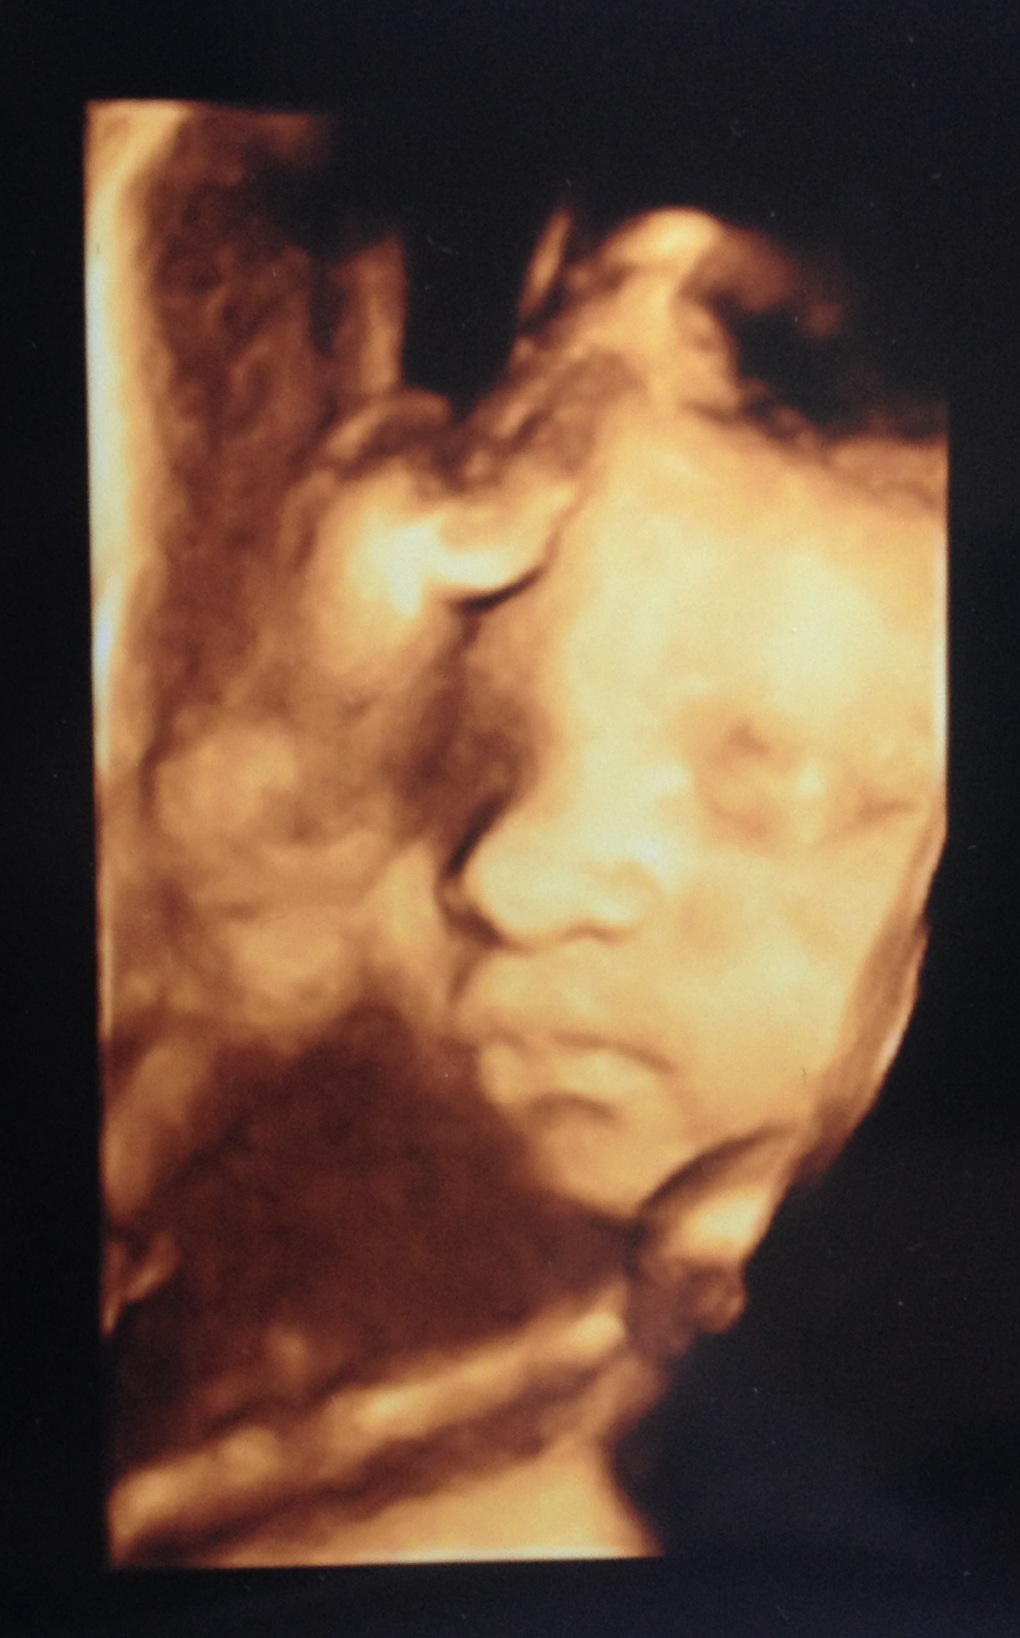

Here is out sweet little girl trying to hide from the camera

I'll be 31 weeks when we go I hope she's not too big.